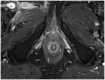

Although a rare disease, anal cancer is increasingly being diagnosed in patients with risk factors, mainly anal infection with the human papilloma virus. Magnetic resonance imaging (MRI) with external phased-array coils is recommended as the imaging modality of choice to grade anal cancers and to evaluate the response assessment after chemoradiotherapy, with a high contrast and good anatomic resolution of the anal canal. MRI provides a performant evaluation of size, extent and signal characteristics of the anal tumor before and after treatment, as well as lymph node involvement and extension to the adjacent organs. MRI is also particularly helpful in the assessment of complications after treatment, and in the diagnosis for relapse of the diseases.